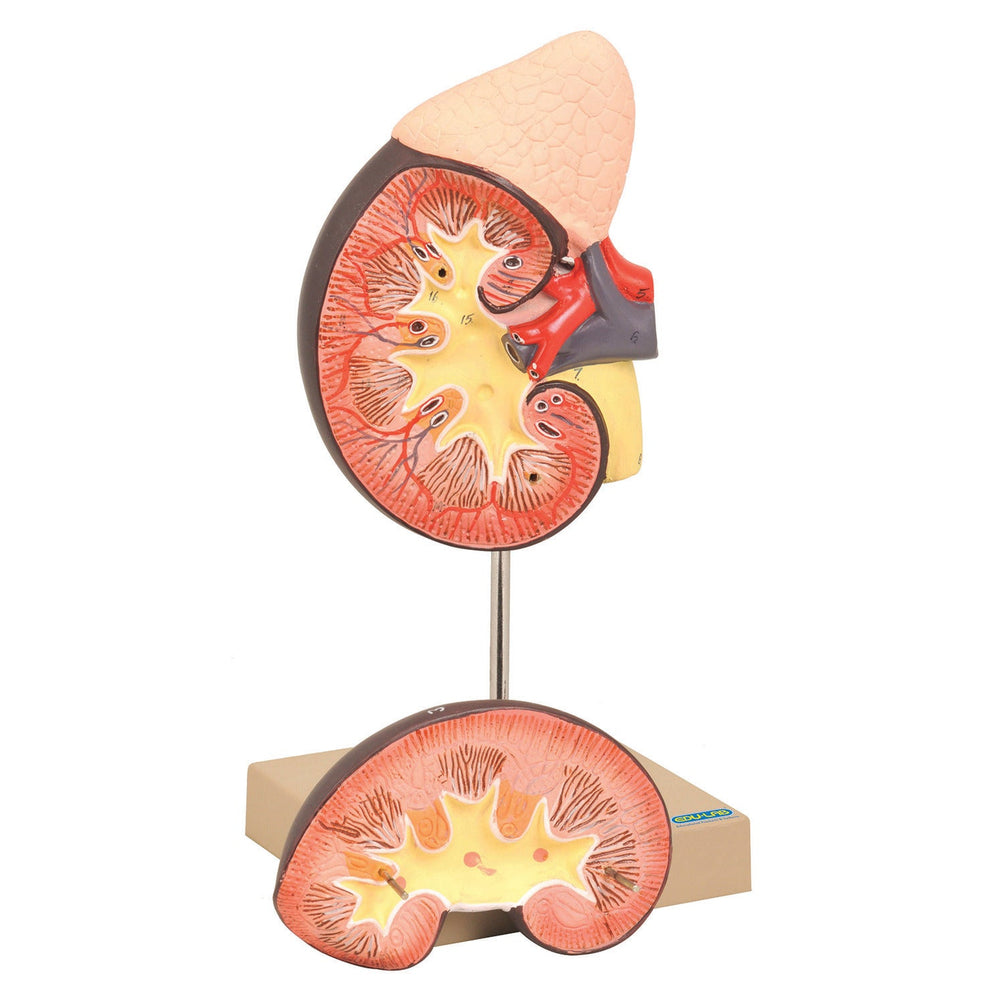

Description

xShows kidney with adrenal gland as well as renal and adrenal vessels and upper portion of urethra. Front half of kidney is removable to show cortext medulla and vessels as well as renal pelvis. Mounted on base and supplied with key card.